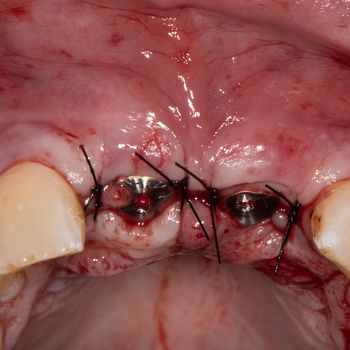

Zunächst erfolgte die schonende Extraktion der Zähne 11 und 21. Präoperativ wurde vom Zahntechniker ein herausnehmbares, auf Klammern dental abgestütztes Provisorium angefertigt, dass am Ende der Extraktion eingesetzt wurde. Für die detaillierte Planung der Implantat-gestützten Rekonstruktion wurde ein Backward Planning angewandt. Nach Anfertigung eines diagnostischen Wax ups wurde eine Bohrschablone als Orientierungshilfe angefertigt. Gemäss einer verzögerten Sofortimplantation erfolgte acht Wochen nach der Zahnextraktion die Implantation in Lokalanästhesie. Klinisch zeigten sich reizlose Wundverhältnisse bei ausreichend horizontalem und deutlich reduziertem vertikalem Knochenangebot (Abb. 3, 4). Der Patient wurde präoperativ darüber aufgeklärt, dass die Augmentation nach Möglichkeit mit der Implantation kombiniert werden sollte. Für den Fall, dass das lokale Knochenangebot ein gleichzeitiges Vorgehen nicht ermöglichen sollte, würde zunächst die Augmentation und etwa vier Monate später die Implantation erfolgen. Nach Abpräparation des Mukoperiostlappens zeigte sich in regio 11 und vor allem in regio 21 ein vestibuläres Knochendefizit, wobei die interdentalen Knochenlamellen regio 12 bis 22 noch vorhanden waren (Abb. 5). Aufgrund der Tatsache, dass sich der ossäre Defekt nur auf die vestibulären Knochenlamellen beschränkte, erfolgte die Augmentation gleichzeitig mit der Implantation. Mit Hilfe der zuvor angefertigten Orientierungsschablone konnten zwei Keramikimplantate mit einem 2-teiligem Implantatdesign und mikrorauer Oberfläche in einer optimalen prothetischen Position und Angulation eingesetzt werden (Abb. 6) (Pure Implantat, ZLA Oberfläche, Institut Straumann AG). Beide Implantate konnten primärstabil inseriert werden, jedoch zeigte vor allem das Implantat in regio 21 ein deutlich ausgeprägtes Knochendefizit (Abb. 7). Zur Rekonstruktion der vestibulären Knochenlamellen wurden mit dem Piezosurgery Gerät (Mectron Deutschland) von der vestibulären Kieferhöhlenwand am Übergang vom Processus alveolaris zum Processus zygomaticus zwei Knochenstücke entnommen und jeweils vestibulär der Implantate mit einer Osteosyntheseschraube im Sinne der Schalentechnik nach Khoury fixiert (Abb. 8, 9, 2b). Anschliessend wurden der Spalt zwischen den Implantaten und den Knochendeckeln mit autologen Knochenspänen – die zuvor mit Hilfe des Safescrapers (Safescraper Twist, Imtegra) entnommen wurden – aufgefüllt und mit einer resorbierbaren Kollagenmembran abgedeckt (Jason membrane, Botiss Biomaterials GmbH) (Abb. 10, 11). Nach erfolgter Periostschlitzung konnten die Wundränder spannungsfrei adaptiert und eine transgingivale Einheilung gewährleistet werden (Abb. 12). Um eine frühzeitige Belastung der Implantate zu verhindern wurde das bereits bestehende Provisorium basal ausgeschliffen und unmittelbar postoperativ wiedereingesetzt. Die Nahtentfernung erfolgte am zehnten postoperativen Tag. Aufgrund der gleichzeitig durchgeführten Knochenaugmentation wurde eine unbelastete Einheilzeit von vier Monaten gewählt.